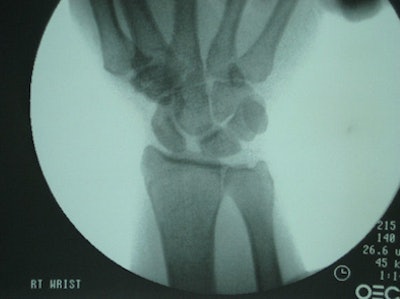

In the research, posteroanterior radiographs of both wrists, with and without grip views, were taken to determine the scapholunate interval. A clinician then used fluoroscopy to manipulate patients' wrists to obtain the maximum scapholunate distance with and without patient grip. Flouroscopic images were digitized for measurement and a radiographic ruler was used for calibration.

In the review of 26 patients, the researchers found that an overlap of the scaphoid and lunate, which prevented measuring the scapholunate interval, occurred in 13% (14 of 104) of all plain radiographs taken. There was no overlap in the fluoroscopic images.

Fluoroscopy also was able to reveal a scapholunate space greater than 2 mm in the wrists, while only 28% (five of 18 wrists) of plain radiographs displayed a scapholunate space greater than 2 mm. The average space measured by plain radiographs was 1.23 mm, compared with 2.23 for fluoroscopy.

| The two clinical images show the difference in a plain radiograph (above) and fluoroscopic image (below) of the same wrist and the modalities' ability to show the scapholunate interval. |